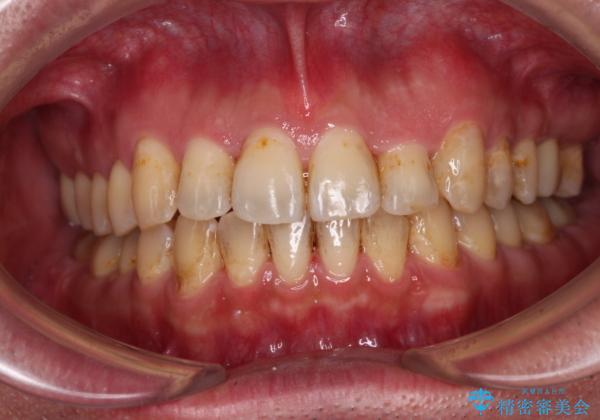

- 虫歯が多く、セラミッククラウンにより虫歯治療を行っている途中で矯正治療をしたいとのことで来院された患者様です。

上顎前歯が舌側に転位しており、なるべく早く楽に矯正したいとのことで、ワイヤー矯正を行うこととしました。

虫歯治療途中の歯は仮歯が装着されていたため、そのまま矯正治療を行い、矯正後に補綴治療を行うこととしました。

インビザライン矯正では苦手とする舌側転位した前歯をスムーズに改善することができました。

矯正治療により歯磨きがしやすくなったので、虫歯予防のセルフケアが行いやすい環境となりました。